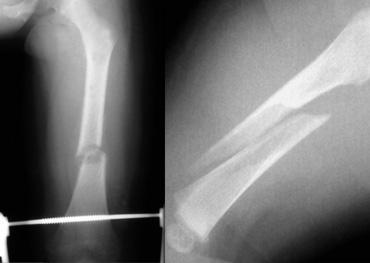

Hai trẻ sơ sinh bị gãy xương đùi. Lạm dụng trẻ em bị nghi ngờ do tuổi của trẻ và bệnh sử không nhất quán được cung cấp bởi cha mẹ.

Gãy xương thân xương (Diaphyseal fractures)

Gãy xương thân xương không đặc hiệu vì chúng có thể xảy ra trong cả chấn thương do tai nạn và không do tai nạn.

Tuy nhiên, trong những trường hợp này, tuổi tác, giai đoạn phát triển của trẻ và bệnh sử lâm sàng rất quan trọng.

Ngã khỏi giường thường không gây ra gãy xương thân xương.

Để gây ra gãy xương thân xương đùi theo chiều ngang, cần phải tác dụng một lực đáng kể.

Gãy xương xoắn là kết quả của lực xoắn vặn.

Mặc dù thường được đề cập, không có bằng chứng nào cho thấy gãy xương xoắn ở chi dưới có độ đặc hiệu cao hơn đối với lạm dụng so với gãy xương chéo hoặc ngang.